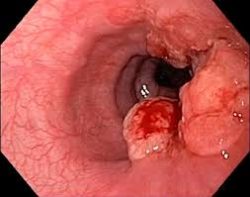

什么是食道癌?

食道癌是食道黏膜细胞恶性转变形成的肿瘤,其中以鳞状细胞癌最常见。该病在台湾男性中尤其普遍,2024年统计显示,全年约2900例新诊断病例,死亡约1800人。

食道癌症状

早期:通常无明显症状,或仅有胃食道逆流、咳嗽、清痰、胸口灼热,容易被忽略。

中期:吞咽固体食物困难、胸口疼痛。

晚期:连吞咽流质食物都困难,伴随体重快速下降、声音嘶哑等明显警讯。

专家建议,从40岁起,每年做一次胃镜检查,必要时搭配染色或高解析度内视镜,特别是出现吞咽不适或异常症状时应立即就医。